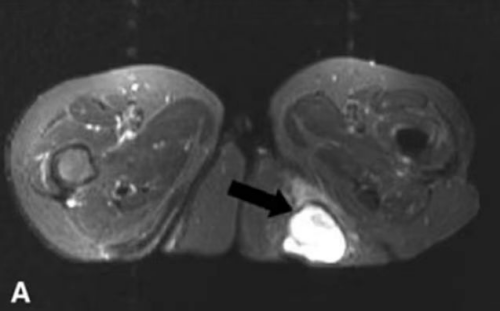

图中箭头所指为“坐骨结节囊肿”

李良军介绍:坐骨结节囊肿,是由于臀部坐骨结节部的滑囊在长时间的过度反复摩擦、刺激、周围肌腱慢性损伤等因素引起滑囊充血、水肿,滑液聚集、囊壁增厚纤维化形成囊肿,常引起臀尖(坐骨结节部)疼痛,坐时尤甚,严重者不能坐下,多发于体质瘦弱而久坐工作的中老年人。